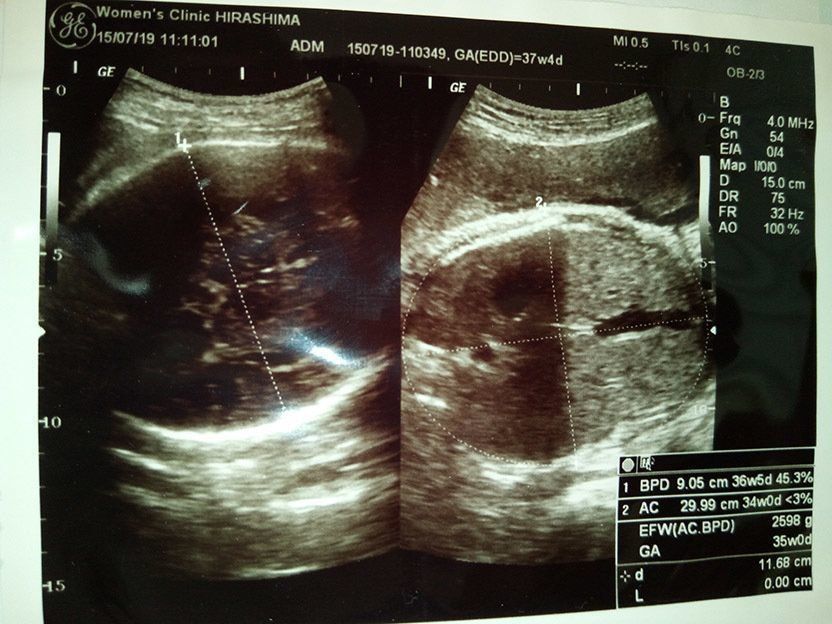

妊娠37週のエコー写真 赤ちゃんの推定体重2598g いつでも出ておいで!

出産するのは実家に近い病院だったこともあり、まだ自宅にいた私は通院回数が増えたことでしんどくなってきていました。でも、まだ里帰りをするのが嫌で自宅で粘っていました。自宅で産気づいたときの対策として、子育てタクシーの対応がある会社へ、今更ながら問い合わせをしました。